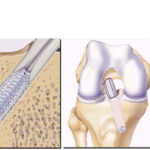

Atualmente, a indicação de tratamento para indivíduos fisicamente ativos que apresentam instabilidade anterior do joelho é a reconstrução ligamentar com enxertos. Os enxertos mais utilizados são os tendões da pata de ganso (semitendinoso e grácil) e o tendão patelar.

A reconstrução do LCA com tendões flexores (grácil e semitendinoso) é uma técnica que apresenta menor morbidade, pós-operatório menos doloroso e melhor estética, por não envolver um acesso anterior no joelho. Funcionalmente, os enxertos mencionados são equivalentes e têm respaldo na literatura.

Os pacientes são orientados a mobilizar e apoiar precocemente o membro inferior acometido, com acompanhamento de fisioterapeuta e educador físico. Geralmente, são liberados para retornar às atividades físicas de contato após 6 meses.